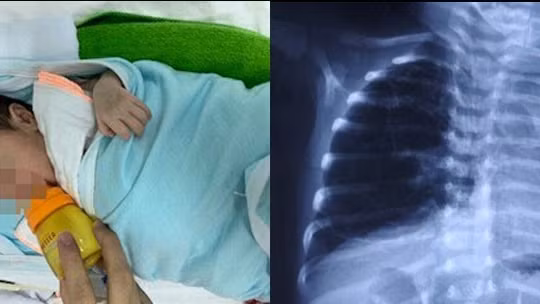

VietTimes -- Nếu ngay trong giai đoạn sơ sinh, trẻ thường khò khè, thở co kéo, tím tái hoặc biểu hiện bệnh giống với các bệnh lý hô hấp khác, viêm phổi tái đi tái lại nhiều lần hoặc có các dấu hiệu như suy hô hấp cấp, nhiễm trùng cấp, có thể trẻ đã bị dị dạng đường dẫn khí phổi bẩm sinh.